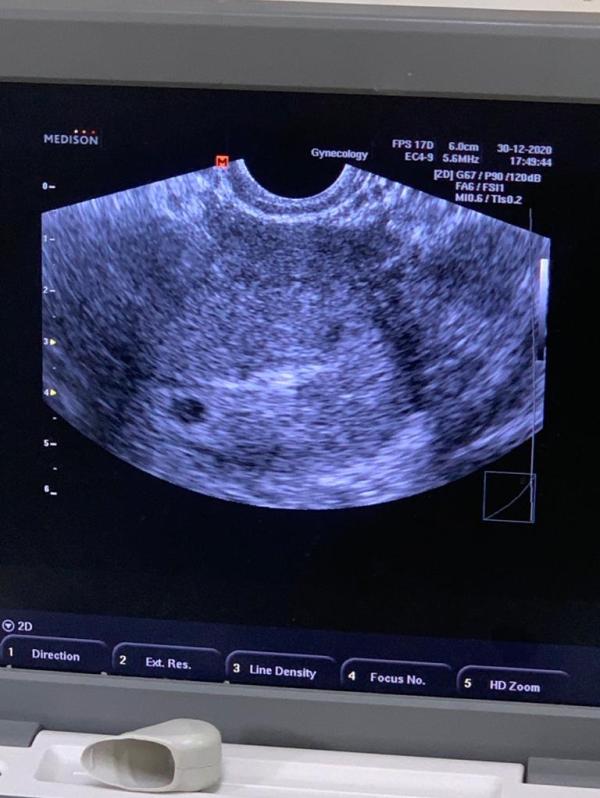

Девочки, врач отправила мне вчерашние фотки.. У кого были двойни, так ли было на 5-6 неделях? Меня смущает их размеры-один побольше, другой поменьше, третьего и не видно..

Вчера порылась в нете, в ютубе, там говориться, что иногда такое бывает что вмдем 2 плодных яйца, но в одном эмбрион.. Со временем второй исчезает.. Я это к чему, у меня таксикоза вообще нет, в роду ни у кого двойняшек нет, возраст не большой, живот вроде не сильно растет, может ли быть ошибка? Может было у кого то такое🙈

Она сказала похоже на тройняшек, но 2 точно есть

@katrin757 аа, поняла вас.. Просто там где побольше, сказала 6 недель и серцебиение уже заметно